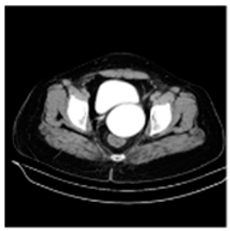

| Original Medical Images | |||||||

| Pair 1 | Pair 2 | Pair 3 | Pair 4 | ||||

![]() (1-9) PSNR = 44.14 | ![]() (1-10) PSNR = 41.90 | ![]() (1-11) PSNR = 40.09 | ![]() (1-12) PSNR = 41.41 | ![]() (1-13) PSNR = 42.24 | ![]() (1-14) PSNR = 40.35 | ![]() (1-15) PSNR = 40.79 | ![]() (1-16) PSNR = 40.84 |

| Shadow Images Produced by Using LSBs | |||||||

![]() (1-17) PSNR = 26.35 | ![]() (1-18) PSNR = 25.49 | ![]() (1-19) PSNR = 23.57 | ![]() (1-20) PSNR = 24.19 | ![]() (1-21) PSNR = 24.79 | ![]() (1-22) PSNR = 24.23 | ![]() (1-23) PSNR = 23.26 | ![]() (1-24) PSNR = 24.42 |

| Shadow Images Produced by Using Middle Bits | |||||||

![]() (1-25) PSNR = 18.97 | ![]() (1-26) PSNR = 19.95 | ![]() (1-27) PSNR = 14.10 | ![]() (1-28) PSNR = 13.84 | ![]() (1-29) PSNR = 16.66 | ![]() (1-30) PSNR = 13.23 | ![]() (1-31) PSNR = 13.38 | ![]() (1-32) PSNR = 14.75 |

| Shadow Images Produced by Using MSBs | |||||||